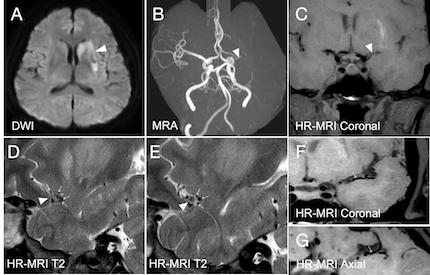

Abstract Body: Background and purpose: Deep tiny flow voids (DTFVs) are a specific type of collaterals surrounding chronic steno-occlusive middle cerebral artery (MCA), which can be identified on high-resolution magnetic resonance imaging (HR-MRI). This study aimed to investigate the presence of DTFVs in patients with acute MCA occlusion and their relevance to clinical outcomes.

Results: One hundred and twenty-three patients with acute MCA occlusion were included. The median age was 61 years (interquartile range [IQR], 51-67 years), and 73.73% of the patients were male. The median time from symptom onset to imaging was 44 hours (IQR, 25-67 hours). Sixty-six patients (53.66%) exhibited DTFVs on HR-MRI. Lower baseline NIHSS scores (4.5 [2-8] vs. 10 [4-14]) and smaller infarct volumes (5.76 [2.79-15.34] cm3 vs. 19.01 [7.16-83.59] cm3) were observed in patients with DTFVs compared to those without. Both multivariable logistic regression (odds ratio [OR]: 6.22, 95% confidence interval [CI]: 1.82 to 21.29, p = 0.004) and linear regression analysis (β: -0.60, 95% CI: -1.06 to -0.14, p = 0.012) indicated that patients with DTFVs exhibited better 90-day functional outcomes. The mediating effect analysis showed that the effect of DTFV on 90-day mRS scores was partially mediated by residual flow distal to MCA occlusion, with a proportion of 30.66% (95% CI: 8.97 to 69.29, p = 0.002).

Conclusions: In our study population, the presence of DTFVs was associated with a favorable outcome in patients with acute MCA occlusion, which may exert a protective effect partly by contributing to the formation of distal residual flow at the occlusion sites. Future studies are needed to investigate the potential of DTFVs in guiding individualized treatment strategies.